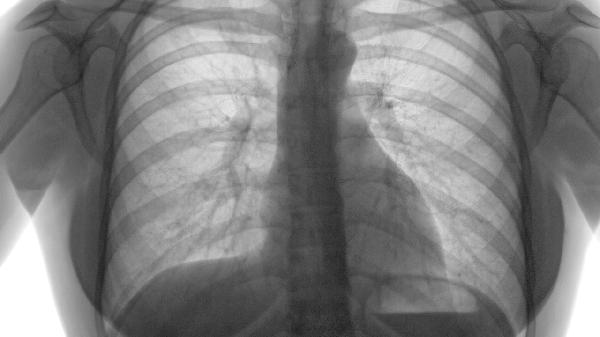

限局性肺气肿是肺组织局部过度充气膨胀的病理状态,可能由慢性支气管炎、支气管阻塞、肺部感染、遗传因素等原因引起。 ...

轻微肺气肿通常不严重,多数患者通过规范管理可长期稳定病情。肺气肿的严重程度主要与病变范围、症状表现、肺功能损害程...